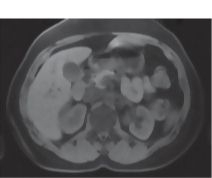

CT Vs. MRI In Abdominal Studies